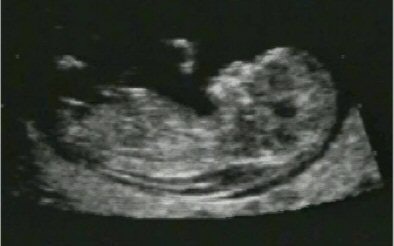

Like maternal serum markers, NT also varies with gestational age or crown-rump length (CRL), and should therefore be considered with those factors. For a given CRL, the larger the NT, the higher the risk of abnormality.

![]() |

| NT/CRL measured on ultrasound is one of the factors determining the risk of abnormalities such as trisomy 21. Image courtesy of Dr Eva Pajkrt, University of Amsterdam. |

In one of the largest NT studies in the world (326 T21 cases in 100,311 women with 96% follow-up), 72% of T21 cases had NT above the 95th percentile. When combined with maternal age for screening, NT had a detection rate of 77% with a false-positive rate of 5% (The Lancet, August 1998, Vol. 352:9125, pp. 343-346). A number of other studies have confirmed the effectiveness of NT in screening, but controversially, a significant number have also demonstrated poor detection rates.